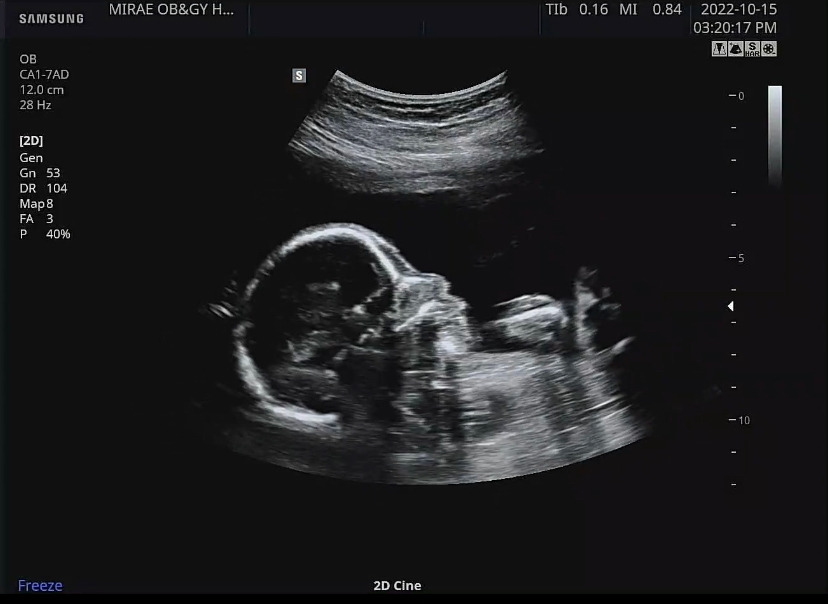

지하철 열심히 타고 병원에 가서 정밀초음파를 했다. 임신 40주의 딱 절반인 20주가 넘어가면서 정밀초음파로 아기의 인중, 귀, 심장(심실과 심방), 심장혈류, 쓸개, 척추, 꼬리뼈, 손발가락, 각종 뼈의 위치, 뇌실의 크기 등등을 볼 수 있었다. 어두운 정밀초음파실에서 10분 정도 정밀초음파를 보고 있자니 어쩐지 졸음이 몰려왔는데 문제는 아기도 졸렸나 보다. 그저 정밀 초음파 시작부터 하품을 시원하게 하며 잠들어버린 아가 덕에 손가락은 보지도 못하고 임신 후 처음으로 아가 주먹을 구경하긴 했지만 그래도 건강하게 잘 크고 있으면 됐다.

12주와 16주차에 한 기형아 검사의 팔로우 업 정도로 혹시 발견하지 못한 선천적 기형이 20주 정밀초음파에서 발견된다고 하기에 (예를 들면 뇌의 이상, 혈류의 이상, 심장의 이상, 척추의 이상 등) 걱정했는데 다행히 무사통과.

정밀초음파에서 처음 본 발가락

그리고 잠들어버린 우리 아가의 옆모습만 한참 구경했다